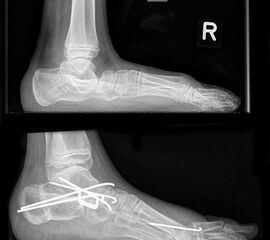

Abbildung 1: Extremer Knick-Hackenfuß beidseits mehr massiven Druckstellen aber ohne Beschwerden. Patient läuft sicher mit Konfektionsschuhen und wünscht keine operative Behandlung.

Abbildung 1